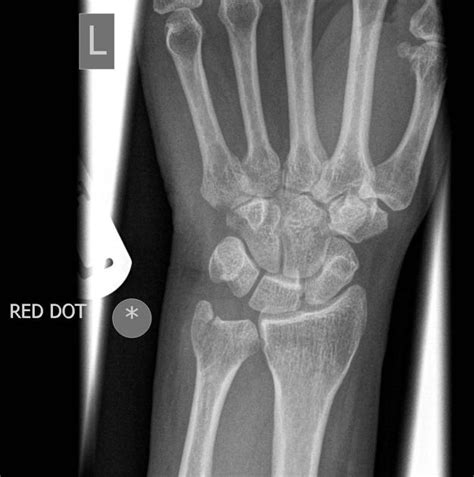

Diagnostic Approach

Diagnosing an ulnar styloid process fracture requires a comprehensive medical evaluation:

- Imaging studies including:

- X-rays